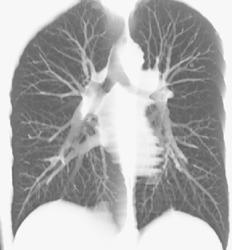

Diagnosis

3D Lung